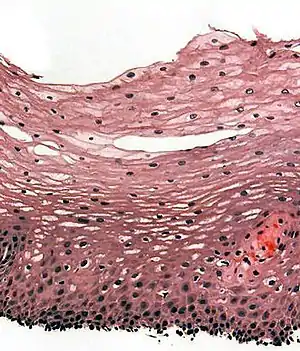

| 复层鳞状上皮(stratified squamous epithelium) | 又名复层扁平上皮,由多层细胞组成,表层为鳞状上皮细胞,基底面的细胞具有分裂能力,产生的新细胞在向表层移行过程中逐渐向鳞状上皮细胞分化。从游离面俯视,可见表层的结构与单层鳞状上皮相似。从切面上看,表层的结构与单层鳞状上皮相似;中间数层为多边形细胞,体积较大;紧贴基底膜的一层细胞具有分裂能力。由于细胞层数较多,为保证营养供应,基底膜常凹凸不平,以扩大接触面积。 | ![]() 复层鳞状上皮(来源于正常食管)HE染色的光镜图 |